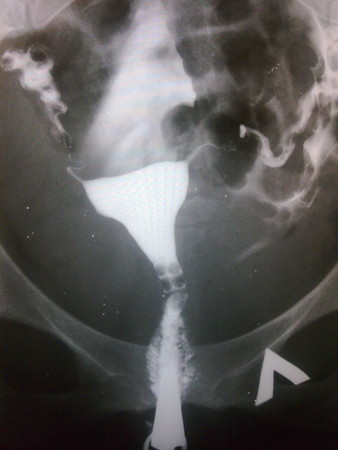

взглянте что такое смещение матки... и вот вам результаты ГСГ ...

Я читала, что если есть смещение матки, то и с проходимостью трубы, в стороную которой она смещена - проблемы. У тебя как раз так и есть, но главное, что левая проходима, а правая - частично!!! Шансы-то есть!!!!

Я наверное профан((( но я ничего не вижу, а матка она тут где? она по середине беленькая да?